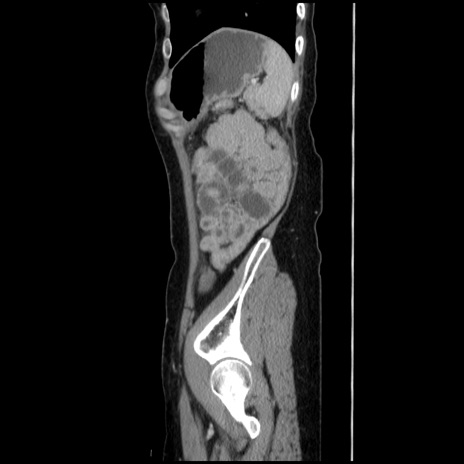

症例32(矢状断像)

【症例】40歳代 女性

【主訴】上腹部痛、嘔気・嘔吐

【現病歴】約9時間前頃から急に上腹部痛、嘔気、嘔吐が出現。改善しないため救急要請。

【既往歴】子宮頚癌(広汎子宮全摘術、放射線療法)、腸閉塞

【身体所見】腹部:平坦、軟、腸雑音亢進、上腹部を中心に腹部全体に圧痛あり。

【データ】WBC 8400、CRP 0.03

横断像